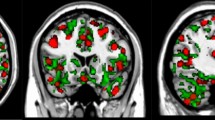

This yielded power maps of the brain regions that are associated with statistically significant wideband spectral power and connectivity in each state in both groups at rest. The pattern of power activity and functional coherence in each state was bilateral, in seven states but was lateralized to one hemisphere in the other five states. The brain states in healthy individuals and those with neuropathic pain corresponded to commonly observed intrinsic resting-state brain networks in the DPC6,40, but since a 12-state solution is used in the model, some high-order networks are divided in subnetworks. The brain states identified in both the HC and neuropathic pain groups included: (1) the posterior and anterior part of the DMN (post DMN, ant DMN); (3) Dorsal/limbic attention; (4) fronto-parietal (FP); (5) motor-control; (6) SN; (7) left and (8) right ascending nociceptive (i.e., sensory) pathway networks (left and right ANP); (9) left and (10) right operculo-insular networks (OP-insular); (11) sensorimotor (SMN), and (12) visual networks (also see Supplementary Tables 1 and 2). Nodes showing significant power in each state tend to accompany increases in phase-locking. Figure 2a shows large-scale brain microstates organization (power and phase-coupling) in HCs (i.e., the basal condition).

a Brain regions with significant power and phase-coupling are represented across a wideband frequency range (1–30 Hz) for the 12 estimated states in n = 40 healthy controls. Node spectral power is relative to the temporal average, and node size is in relation to the mean power (Z score) across states (blue and red colors reflect power that is lower or higher than the average over states, respectively). Edges between nodes show functional connectivity, and only significant and high-valued connections are shown. Significant coherences were mainly found between active nodes in each state. The same 12 states were found in the patients cohort, and the nodes’ repartition was similar across a wideband frequency range. b Spectral power averaged across all brain regions in brain states as a function of frequency (green: delta/theta, blue: alpha, and red: beta). c Spectral profiles of the DMN (post. DMN: blue; ant. DMN: purple), SMN (green), and visual (yellow) states, in terms of power averaged across brain regions, in comparison to the grand average (black line); Standard deviations are represented. *P < 0.001; permutation P value, 5000 bootstrap samples. DMN Default mode network, ANP ascending nociceptive pathway, OP-insular (operculo-insular), SMN sensorimotor, DPC dynamic pain connectome.